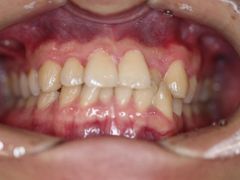

• -德伦口腔

LEE | 19-05-21

报错